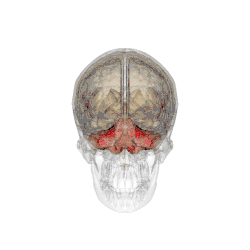

![]() Модель мозга человека, красным выделен мозжечок | |